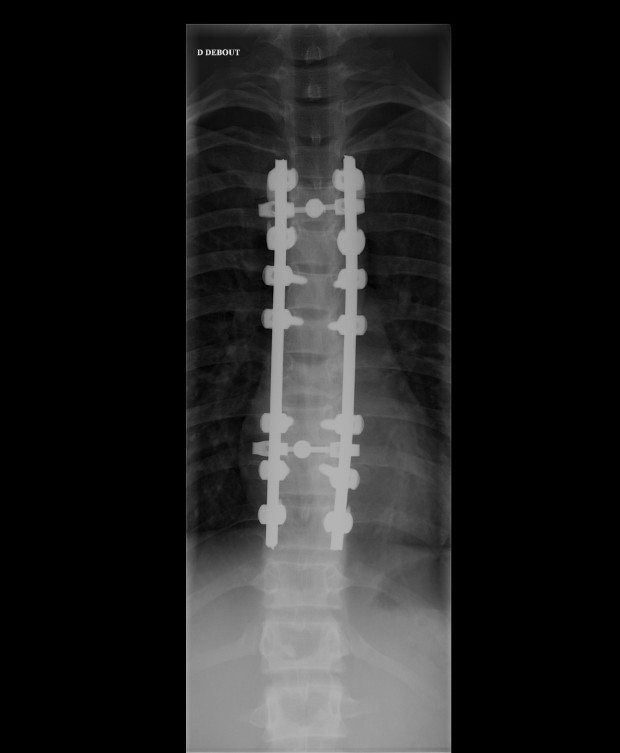

By Wednesday 10th there was a clear plan by the surgeons – Dan relayed to me the intention to fuse some of the vertebrae together – which sent alarm bells off in my head as I was already thinking about Tay’s return to sport. A spinal fusion is something rugby players can and do have, and carry on playing. However given how young Tay is, I didn’t think this was the way to go – however it was then changed to a fixation. This meant they were going to put titanium rods either side of the fracture site. Again, the degree of ‘fixation’ can vary and the intention was to rod the damaged vertebra, the ones immediately above and below. I was really keen to have Tay flown back to UK and taken straight to the back specialist I use, however the insurance would not fly Tay out of France without the operation. This is entirely understandable as the bones can and do displace in flight. Some companies are prepared to have the patient as immobilised as possible and fly them, whilst others insist the surgery is carried out. I reminded everyone involved that the hospital that Tay was being treated in Grenoble likely dealt with 100′s of surgeries similar with recreational skiers throwing themselves down the mountain in the winter and were probably more than capable.

Having had such a major operation, the short term treatment once back in the UK was to rest to allow some healing. Tay had some rudimentary guidelines from the doctors in France, but essentially it was rest he needed. I also advised his parents to take him to the GP as soon as possible, something I wouldn’t normally do but Tay would need some decent post op care, which meant reporting to the GP to get some NHS resources to swing into action. Unfortunately the GP experience was a massive ‘computer says no’. As helpful as the GP tried to be, due to Tay having the operation in France this meant referring him onto a specialist would take a few weeks before he was able to see anyone about his back. Figuring that the GP route would get bogged down in red tape, I’d already placed some calls and got Tay to the one of the WRU ‘go to’ guys for spinal injuries – Dr Stuart James – as we really needed an urgent expert opinion on exactly what operation Tay had carried out on him and what the next steps were. Big thanks to elite physio Tim Atter for helping out with setting all that up. When Tay’s dad sent me the images and scans – it was fairly shocking, even for me.

I actually had never seen that level of fixation in the spine, and even to me it looked a bit ‘over’ fixated and certainly not the relatively minor fixation described by the doctors before the op. I was also thinking about how young Tay was and any considerations needed with growth. Meeting with the specialist surgeon in Wales, he too felt he wouldn’t have gone with quite so much fixation – but every surgeon is different. Regardless of the operation it’s what happens post op and how that’s managed which is going to have the most positive effect. The thing to do now was come up with a plan, so me and team fitness coach Alan Milway sat down and began working it all out…